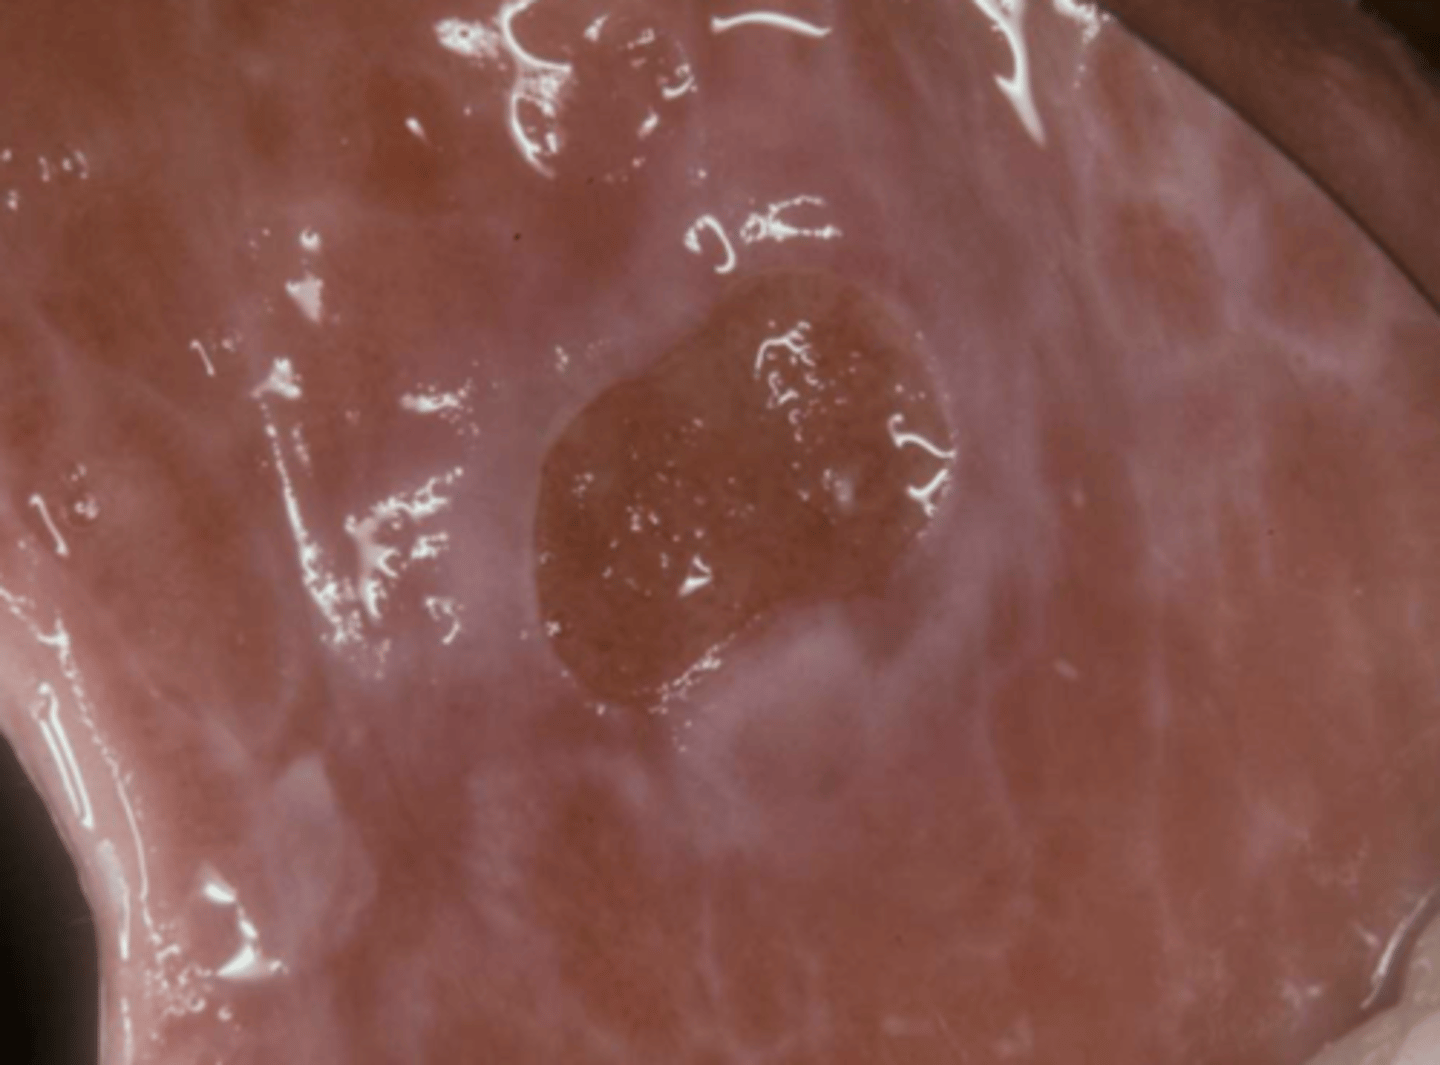

This is the clinical manifestation of which condition?

What condition?

desquamative gingivitis